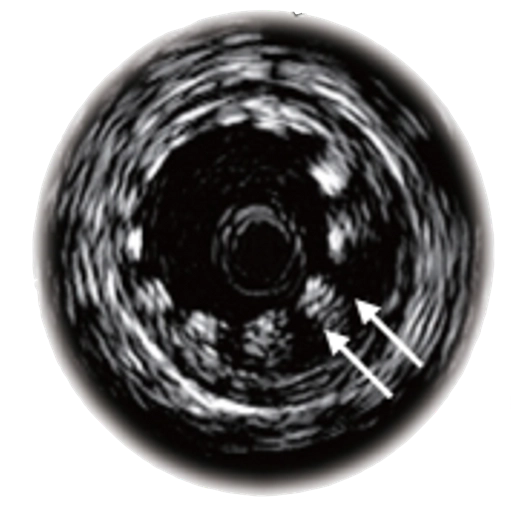

Установленный стент не полностью прилежит к стенки артерии (указано стрелками), что повлияет на отдаленный прогноз и срок службы стента.

Другой ценностью метода является оценка результата стентирования коронарных артерий благодаря высокой разрешающей способности в несколько микрон. Такая разрешающая способность позволяет увидеть клетки сосудов сердца, что делает ВСУЗИ по-настоящему уникальной технологией.

При проведении ВСУЗИ первым этапом к устью коронарной артерии подводится катетер. За место сужения заводится тонкий металлический проводник диаметром 0,3 мм, по которому проводится ультразвуковой датчик. Все изображения передаются на специальное оборудование, где и происходит обсчет полученных данных.